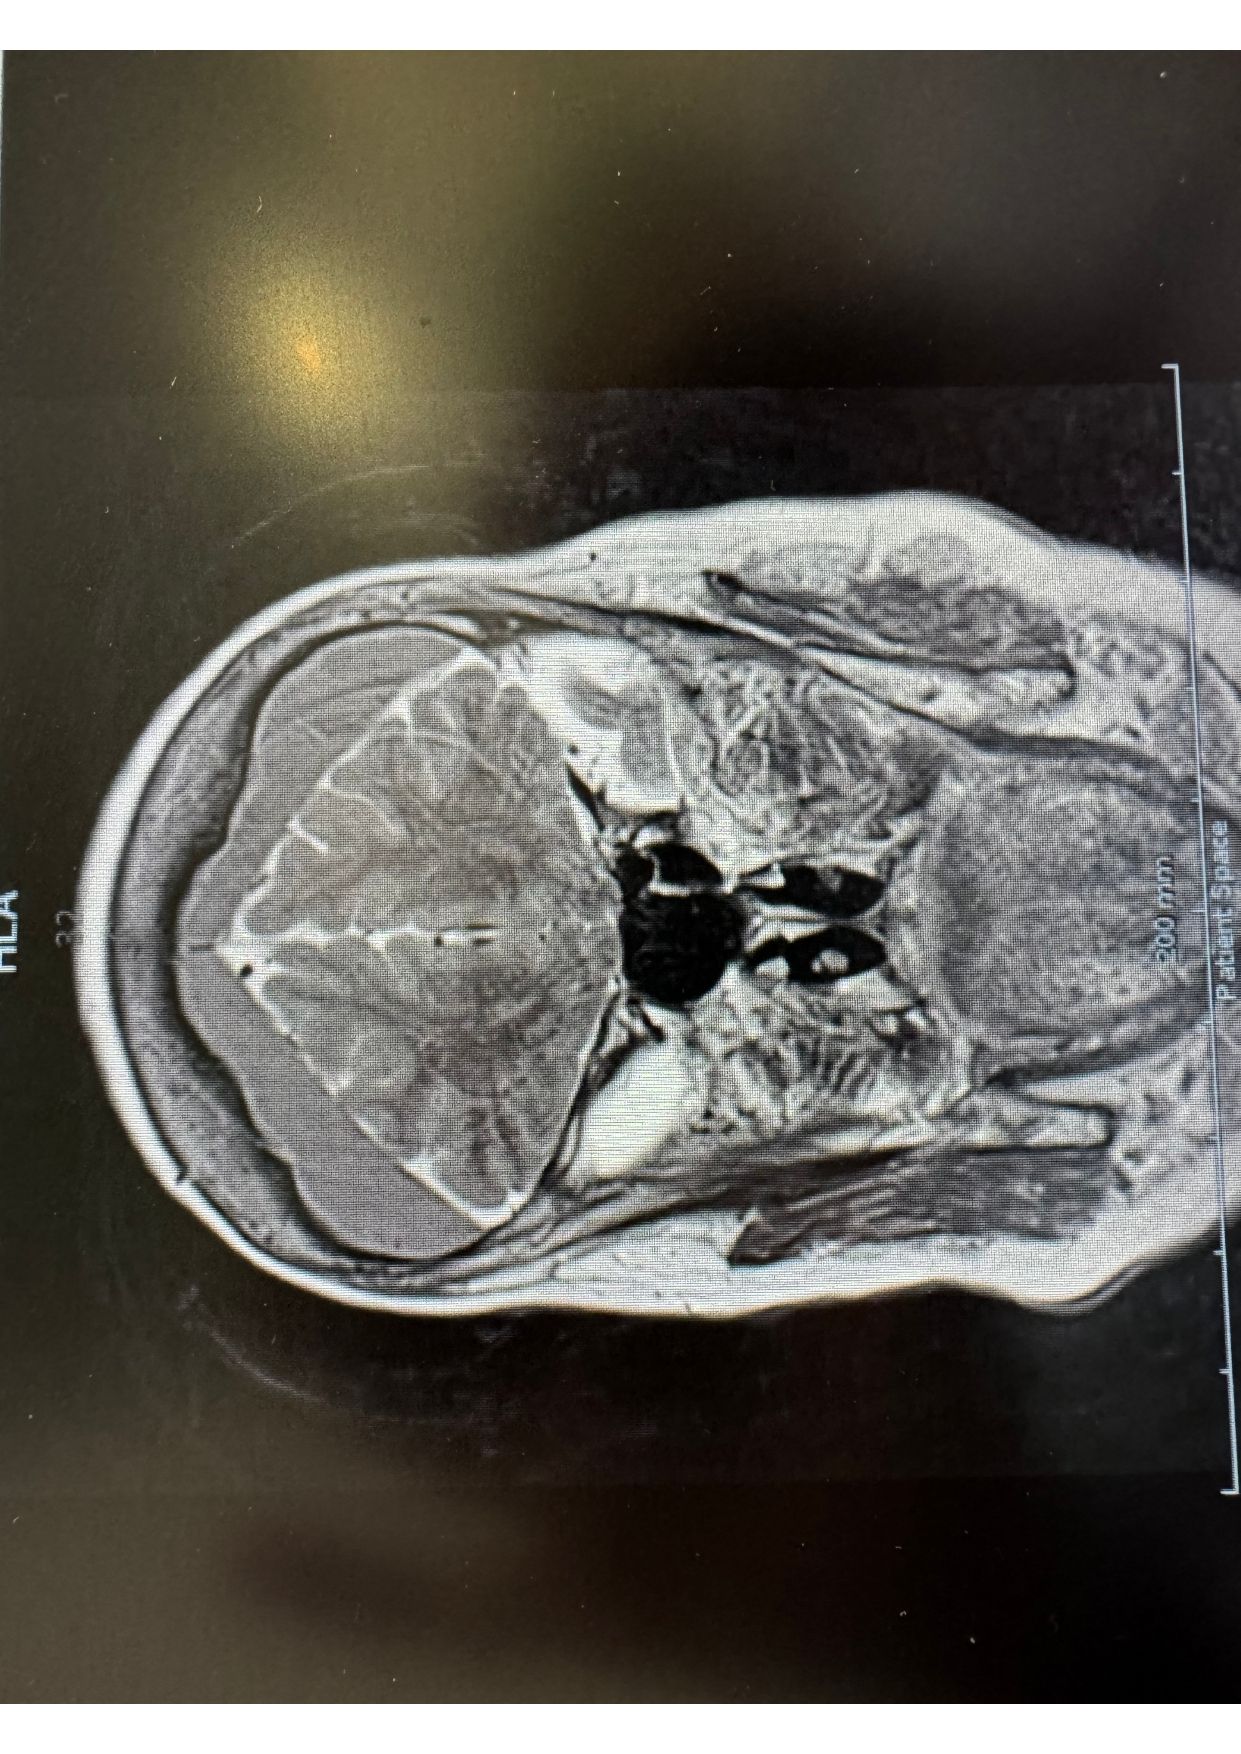

Patologias Tumoral Crânio Encefálica e Raquidiana

- Diagnóstico e tratamento de tumores que afetam o cérebro e a coluna vertebral.

Patologia Degenerativa da Coluna Vertebral

- Tratamento de doenças que afetam a estrutura e função da coluna, com potencial impacto na qualidade de vida.